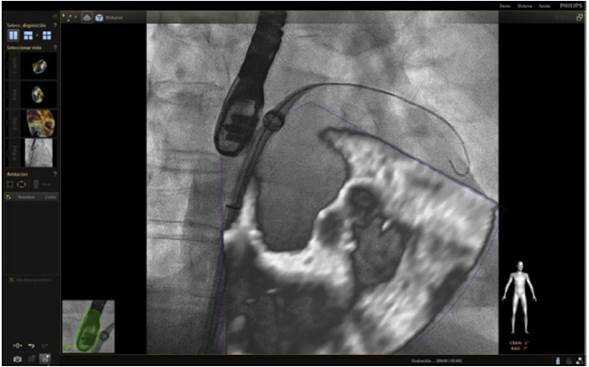

En respuesta a las necesidades de buenos resultados y seguridad para el paciente durante la realización de procedimientos complejos, se desarrolló un software capaz de fusionar la fluoroscopia y la ecocardiografía transesofágica 2D/3D13 en una sola imagen (figs. 2 y 3). Viene utilizándose cada vez con más frecuencia, con múltiples reportes en la literatura, pues ha mostrado sus buenos resultados de eficacia y especialmente de seguridad, dando la posibilidad de su implementación en la rutina diaria.

Figura 2 Imagen de fusión en ecocardiograma transesofágico 3 D cuatro cámaras; se observa guía que pasa a través de septo interauricular durante colocación de Mitraclip.